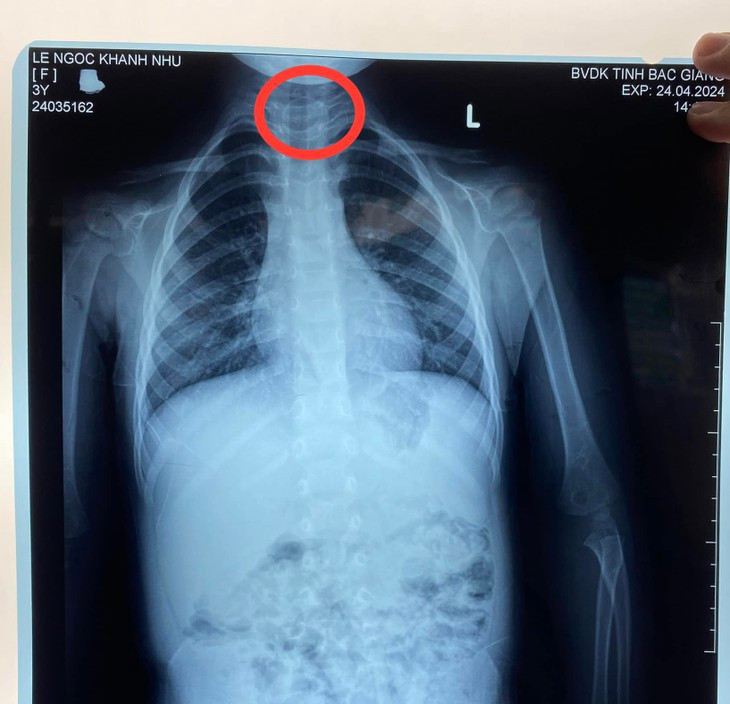

Tại Khoa Cấp cứu, các bác sĩ thăm khám và nghi ngờ có dị vật thực quản. Bệnh nhi được chụp X-quang và kết quả cho thấy có dị vật hình tròn cản quang nằm ngang đoạn 1/3 trên thực quản ngang mức cột sống T1-2. Sau khi hội chẩn, các bác sĩ đã chỉ định nội soi can thiệp gắp dị vật đường tiêu hoá và chuyển bệnh nhi lên khoa Thăm dò chức năng để tiến hành.

| Đồng xu trong thực quản bé gái - Ảnh: BVCC |